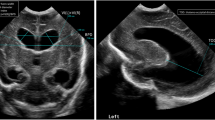

Bilateral grade III hemorrhage in a 19-day-old girl (born at 30 weeks’ gestation) who underwent gray-scale US as follow-up for post-hemorrhagic hydrocephalus caused by choroid plexus hemorrhage. a Mid-coronal plane of the brain demonstrates dilated ventricular system with mildly echogenic ependymal lining from ventriculitis in the setting of intraventricular blood products (solid arrows), in keeping with grade III intraventricular hemorrhage. There is altered morphology of the bilateral choroid plexuses of higher echotexture (dotted arrows) than the intraventricular blood products. b Coronal unenhanced brain CT obtained 4 days after the brain US demonstrates dilated ventricular system. Bilateral choroid plexus is faintly visualized (dotted arrows) but the intraventricular blood products are difficult to discern because of the technique. Subtly hyperdense left frontal horn blood products are evident (solid arrow)

Grade IV intraventricular hemorrhage (IVH) in a 22-day-old girl (born at 23 weeks’ gestation) with history of IVH and ventriculomegaly. She underwent gray-scale brain US for follow-up. a Coronal image demonstrates heterogeneous echogenicity in the left germinal matrix caused by hemorrhage (solid arrows) and right periventricular/intraventricular echogenicity (dotted arrows) from germinal matrix hemorrhage and parenchymal venous hemorrhagic infarct in the setting of grade IV IVH. b, c Sagittal images of the right (b) and left (c) lateral ventricles show the bilateral hemorrhagic blood products of heterogeneous echotexture distending the lateral ventricle (arrowheads)